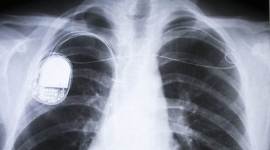

Since surgery to replace the battery can lead to complications, including infection and bleeding, various researchers have tried to build pacemakers that use the natural energy of heartbeats as an alternative energy source.